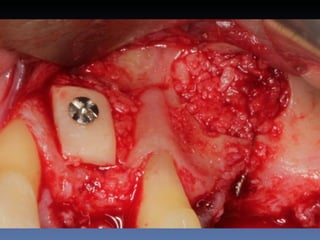

BOX 4

Ville Victorazzo Carmo

Idade – 20 anos

Sexo – Masculino

Raça – Caucasiana

ASA – I

Data- 27-04-2012

Diagnóstico: Desdentado da zona 2.1,

pré-regenerada.

Plano de tratamento: Instalação de implante endo-

ósseos ( 2.1 ) para reabilitação protética fixa.